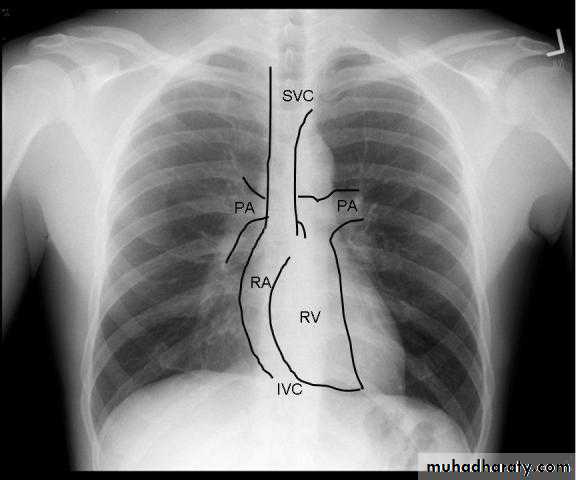

Radiology of the Heart

Chest X-ray: Postero-anterior view (PA view):Size of the heart

Shape of the heart

Specific chamber enlargement

Status of the pulmonary circulation

RV enlargement:Cardiomegaly

Straightening of the left heart border

Apex displaced upwards

Right atrial enlargement:

Prominence of the right border of the heart